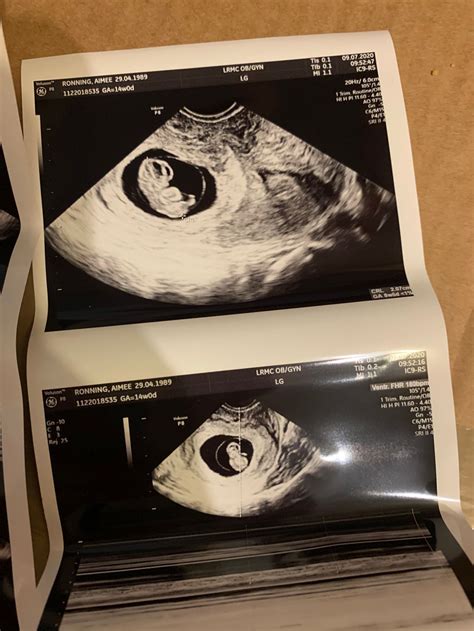

Interpreting the Results of a 6 Week Ultrasound

The results of a 6 week ultrasound provide valuable information about the early stages of pregnancy. Here are some key findings to look for:

• Gestational Sac: The presence of a gestational sac confirms the pregnancy. It appears as a small, fluid-filled structure within the uterus.

• Yolk Sac: By week 6, a yolk sac may be visible. This structure provides early nutrition to the embryo and is a positive sign of a healthy pregnancy.

• Fetal Pole: The fetal pole is the earliest visible structure of the embryo. It appears as a small, curved line within the gestational sac.

• Fetal Heartbeat: A fetal heartbeat may be detectable by week 6, although it is more commonly seen by week 7. The heartbeat appears as a flickering motion on the ultrasound screen.